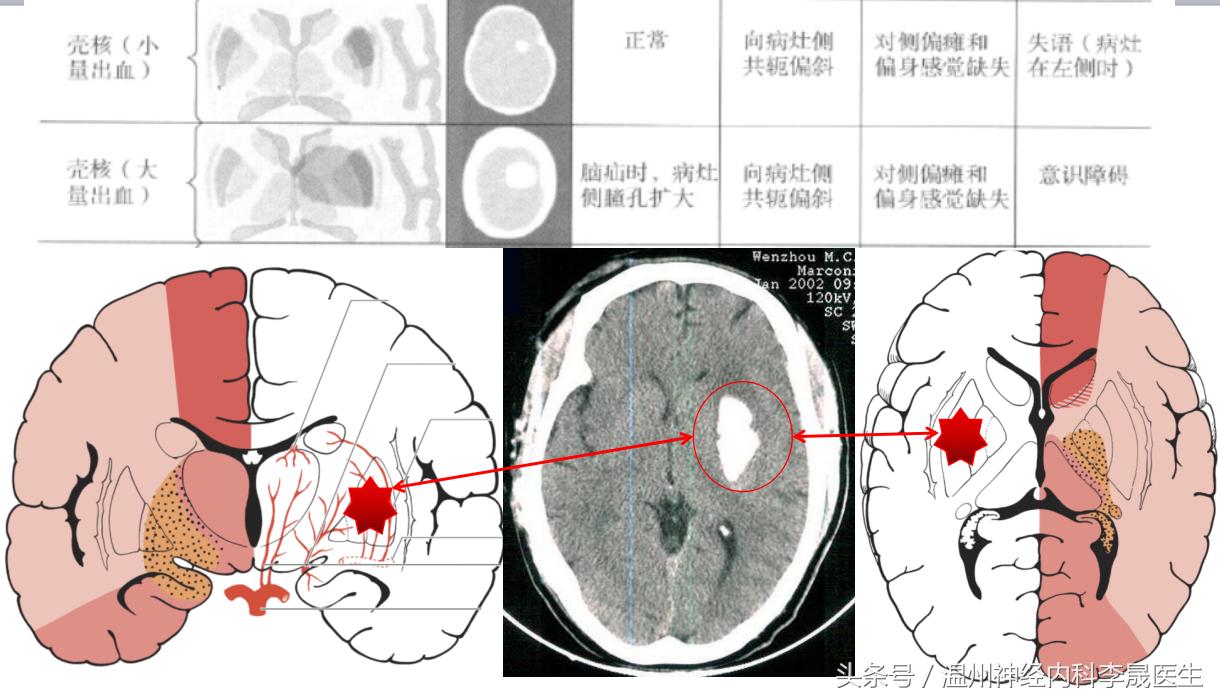

2)壳核出血

①豆纹动脉外侧支破裂,占50~60%

②突发“ 二/三偏”征: 可伴向病灶侧凝视(双眼凝视病灶侧) 优势半球损害有失语;

③出血量大:有意识障碍,可破入脑室;

出血量小:可呈纯运动性/纯感觉性障碍,无头痛、呕吐等,与腔梗不易区分。

壳核出血

壳核出血(大)

壳核出血(A)小壳核范围内的出血,(B)侵犯了内囊,(C)血肿压迫侧脑室

轴位脑切面示意图,(1)前部型累及壳核前部和内囊前肢;(2)中间型包括内囊膝,苍白球和壳核的中间部分(3)后部型累及内囊后肢远端且常累及是辐射并向颞叶蔓延